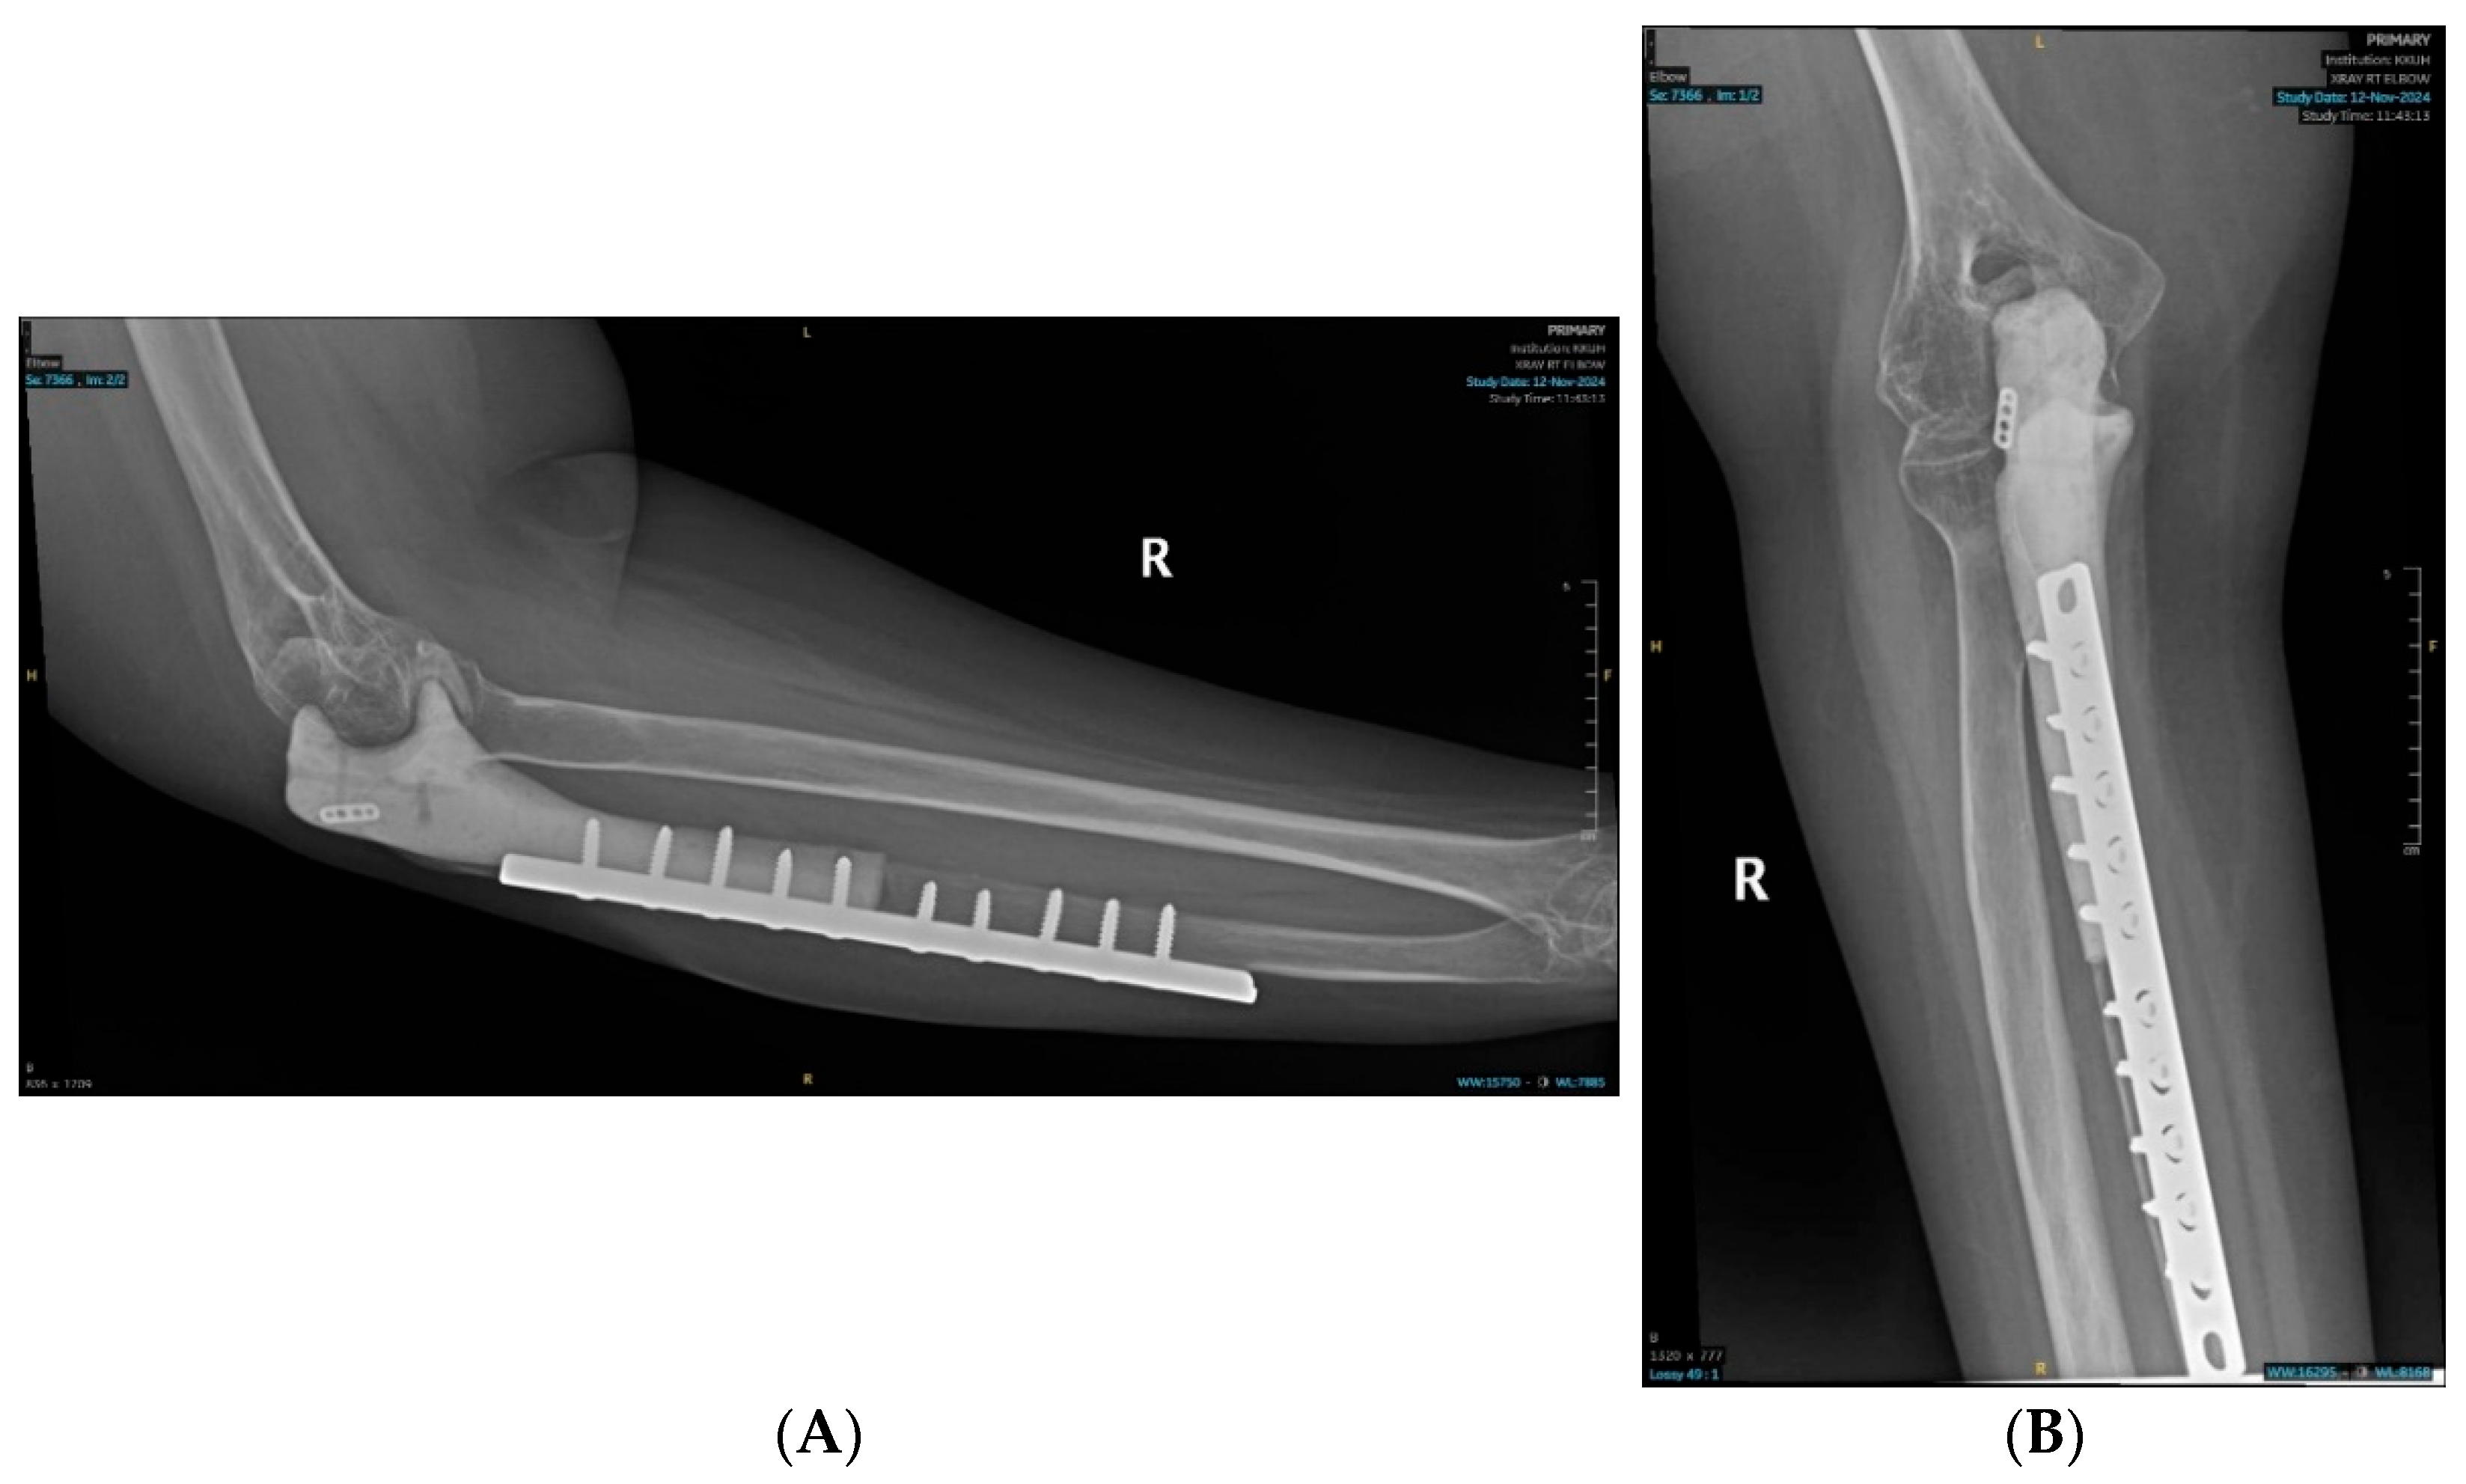

2.1. Surgical Technique

2.2. Postoperative Course and Histopathology